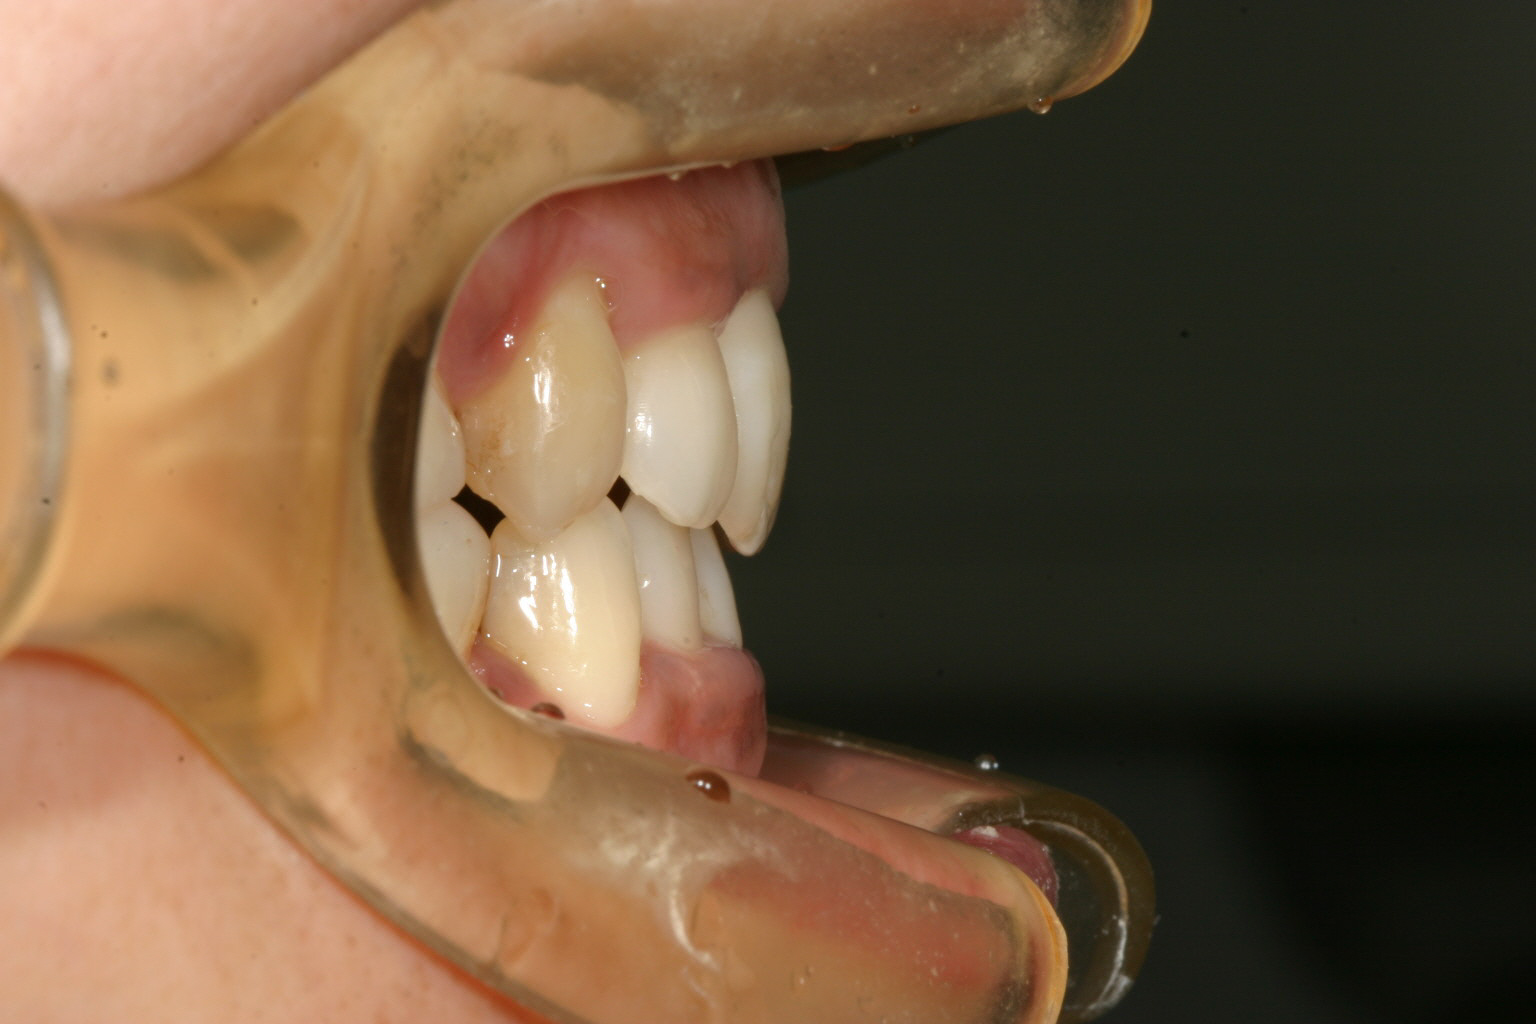

綺麗な被蓋関係になってます。

この時代はまだ加速矯正装置というものがなかったため、抜歯後前歯にワイヤーを使って

そこそこ犬歯移動を行った後インビザラインと言う方法を行いました。

今では第一選択枝はインビザライン+加速矯正装置となりもっと短期間で終われる時代になりました。